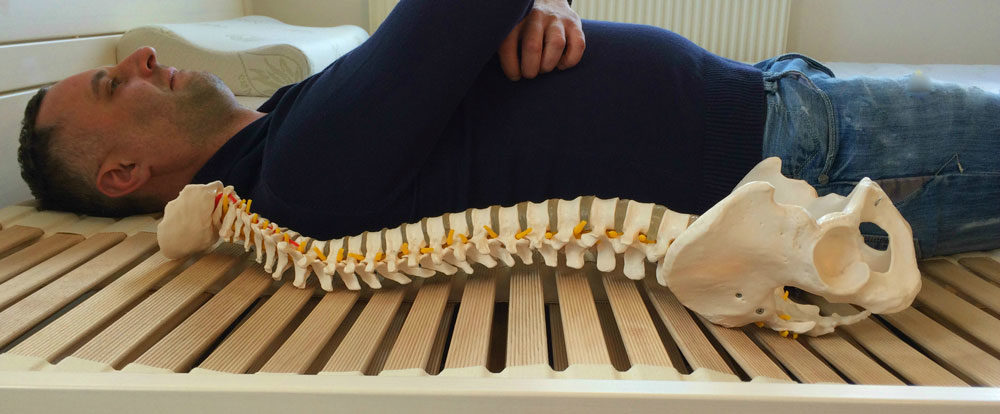

Its special finish and suspension means they are able to carry out vertical, transverse and rotational movement. Regardless weight, shape or position on the bed, it always keeps the spine in the ideal position. Furthermore, it makes perfect weight shifting.

The slat base adapts perfectly to the shape of the user’s body. It provides perfect, equal support to the spine along its full length as well as exceptional lower back support.

The vertebral discs will take up the optimal position during sleep avoiding their degeneration. Importantly, decreasing the load strain and thereby ensuring that no harmful tension points develop. The Demko Bed-System evenly distributes the weight on the bones, the ligaments, the muscles linking them. As well as on the muscles surrounding the spine and the area around the joints. As a consequence, the blood supply will be perfect as will be the removal of inter-tissue waste material through the veins and lymph vessels. At the same time the slat base also stretches the spine longitudinally, moving the vertebrae and articular discs away from each other. The arteries are straightened out and the local blood pressure will decrease and supply of nutrition to the articular discs will increase.